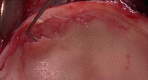

Methods: This was a retrospective comparative study of 21 hips (20 patients with symptomatic anterior FAI) without osteoarthritis on anteroposterior radiographs. Morphological MRI and dGEMRIC (3.0-T, 3-dimensional [3D] T1 maps, dual-flip angle technique) of the same hip joint were compared. Intraoperative acetabular cartilage damage was assessed in patients who underwent surgical treatment. Computed tomography (CT)-based 3D bone models of the same hip joint were used as the gold standard for the detection of impingement, and dGEMRIC indices and zones of morphologic damage were compared with the CT-based impingement zones.

Results: Of the 21 hips, 10 had cam-type FAI and 8 had pincer-type FAI according to radiographs. The mean age was 30 ± 9 years (range, 17-48 years), 71% were female, and surgical treatment was performed in 52%. We found a significantly higher sensitivity (69%) for dGEMRIC compared with morphological MRI (42%) in the detection of cartilage damage (P < .001). The specificity of dGEMRIC was 83% and accuracy was 78%. The mean peripheral acetabular and femoral dGEMRIC indices for clock positions with impingement (485 ± 141 and 440 ± 121 ms) were significantly lower compared with clock positions without impingement (596 ± 183 and 534 ± 129 ms) (P < .001). Hips with cam-type FAI had significantly lower acetabular dGEMRIC indices compared with hips with pincer-type FAI on the anterosuperior clock positions (1 to 3 o'clock) (P = .018).